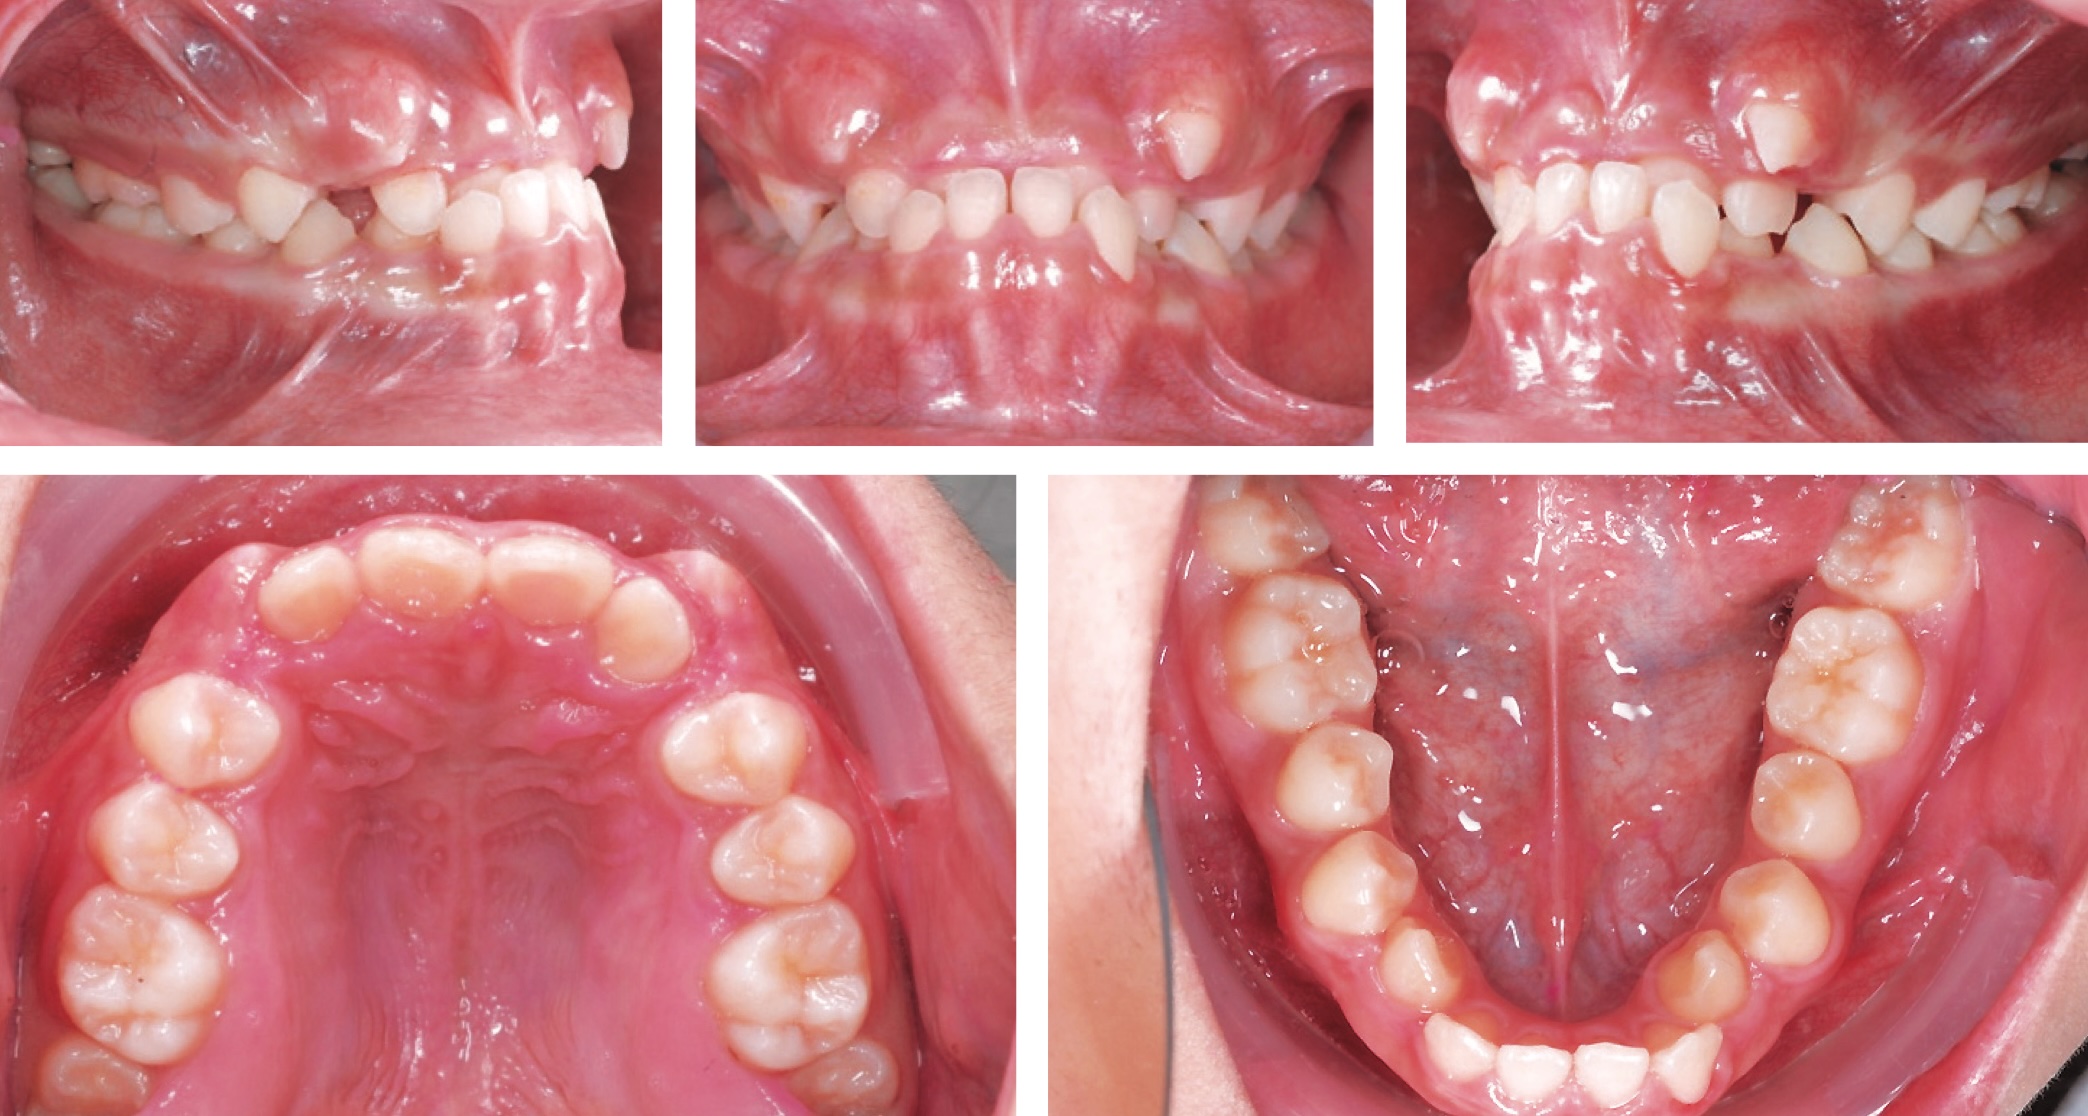

Del número más reciente del JDO (editado por el Dr. Chris Chang), traemos este artículo de nombre Non-Extraction Treatment of Pseudo-Class III Anterior Cross-Bite Complicated by Severe Crowding, Deep-Bite and Clenching. En el cual nos muestan el tratamiento de un joven de 13 años de edad, pseudoclasee 3, mordida profunda y cruzada anterior, el tratamiento fue llevado sin extracciones. Se utilizo autoligado pasivo, bite-turbos en molares, elásticos cortos clase 3 tempranos.